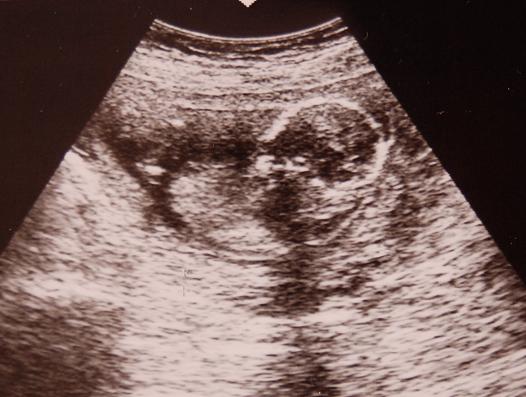

Doki bácsimnál rákukkantottunk Maszatkára, de nem sokat láttunk. elég xar a gép és Baba is elbújt rendesen. Akartam képet kérni és hogy esetleg kukkantsunk már be a lába közé de kb. az volt a válasz, hogy ne kérjek ilyen extrát, örül ha azt látja hogy hogy van bennem a gyerek!

Buksiját tudtuk csak lemérni, aszerint tegnap volt 16+2, tehát teljesen korának megfelelő.